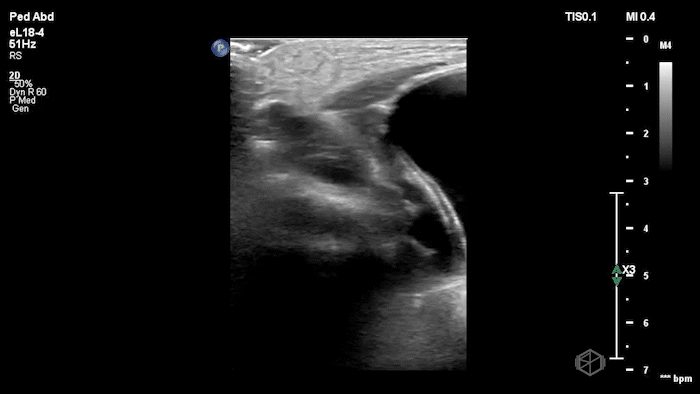

05 - What is being examined and what is the diagnosis?

Phlebitis (no thrombus present to make it thrombophlebitis)